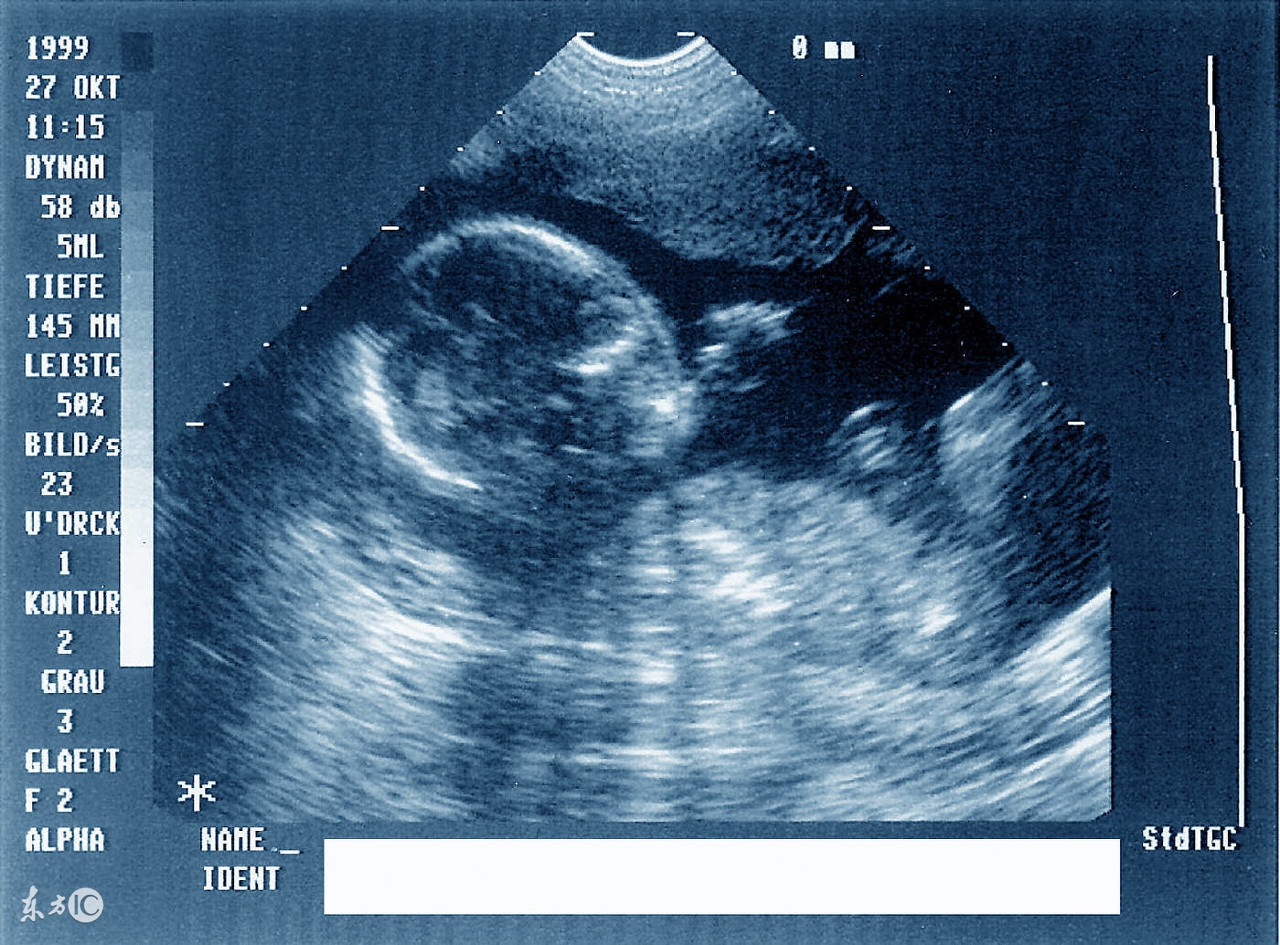

周力学介绍说,第一次产前超声检查最好选择在停经六七周,选择经阴道彩超或者经腹部彩超,由于此时孕囊和宝宝较小,阴道超声下可能显示会更清晰。此时宫腔内已经可以看到妊娠囊,妊娠囊内可以看到胚芽,也就是宝宝早期的形态,如果位置好的话还看得见宝宝原始心管搏动。

早期产前超声发现了有心管搏动的胚芽后,准妈妈们可以准备预约第二次产前超声(孕13+6周III级彩超检查)了,这次时间位于停经11-13+6周。早期,这项检查的出现主要通过测量宝宝颈项透明层(也就是大家听得比较多的NT)和胎儿鼻骨来进行宝宝染色体疾病的筛查。目前这项检查也包含早期胎儿畸形的筛查及诊断,例如无脑儿、联体双胎、露脑畸形、各种常见的胎儿心脏畸形、肾脏缺如等。